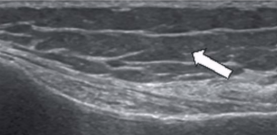

US appearance of tendons

LAX

Linear band of hyperechoic strands and fibrillar pattern, interspersed with relatively hypoechoic connective tissue

SAX

“Whisk-broom” appearance

Hyperechoic foci throughout tendon distribution interspersed by hypoechoic connective tissue

Must maintain uniform thickness throughout except at site of insertion (might broaden)